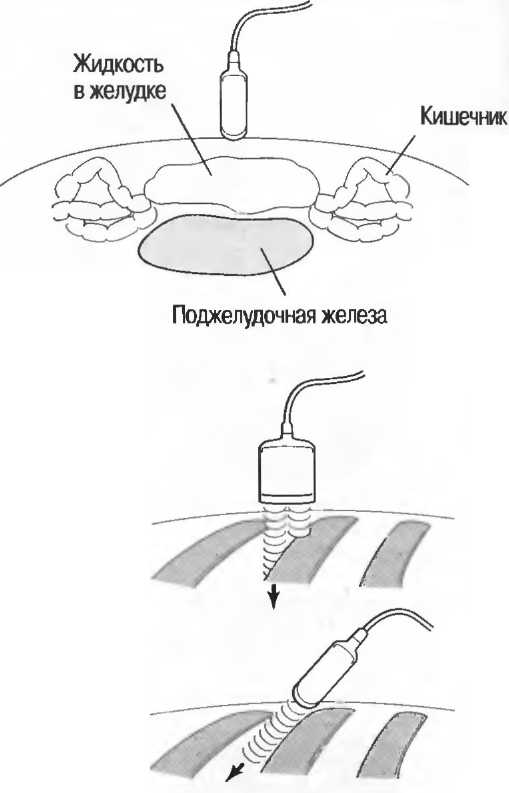

Акустическое усиление и акустическая тень

Чистые жидкости проводят ультразвуковой сигнал без существенного ослабления, поэтому отраженные эхосигналы, идущие от тканей, расположенных за жидкостью, обычно усилены (более яркие). Этот феномен известен как «акустическое усиление» (рис. 10а). Прием достаточного количества жидкости для заполнения желудка дает смещение кишечника, содержащего газ, и тем самым создает акустическое окно. Это особенно полезно для визуализации тела и хвоста поджелудочной железы.

Газ в кишечнике или еще где-либо вызывает появление различных эхографических феноменов. Ультразвуковой луч может рассеиваться, отражаться, поглощаться и преломляться таким образом, что становится практически невозможной визуализация подлежащих структур. По этой причине ультразвук не может быть использован для визуализации нормальных легких или выявления заболевания легких, за исключением объемных процессов, расположенных по периферии органа. Рентгенография грудной клетки в этом случае даст большую информацию.